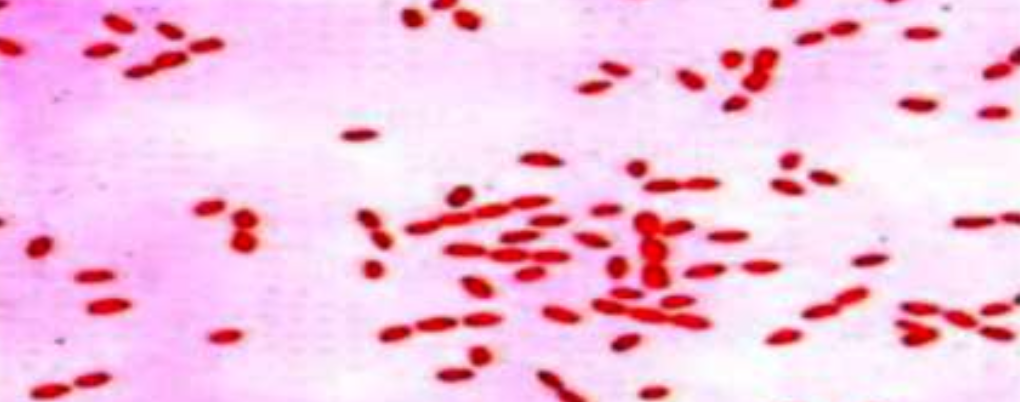

A 30 year old veterinarian complains of general fatigue, malaise, joint pains and lymph node enlargement since many months. Blood culture showed the following bacteria :

A 30 year old veterinarian complains of general fatigue, malaise, joint pains and lymph node enlargement since many months. Blood culture showed the following bacteria :

What is the most likely diagnosis?

Name any risk factor for getting this disease?

- Farmers, vets, and drinking unpasteurized milk

Name any 3 organs or body systems which are affected by this disease in humans?

- Lymph nodes, liver, and spleen

Which is the most commonly used test for diagnosis? Z

- Brucella antibody titers (agglutination test)

Name any 2 medicines used in the treatment of this disease?

- Doxycycline and streptomycin Z